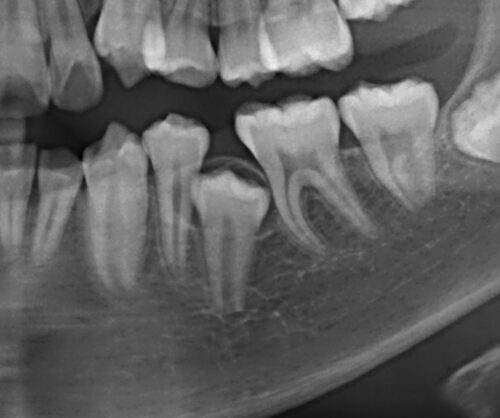

13歳男性、左下5番が萌出不全。エックス線像を見ると両隣在歯に引っかかっており、また歯冠を囲むように嚢胞様の透過像が見られます。

8ヶ月後のレントゲン写真です、しっかりと萌出することができました。